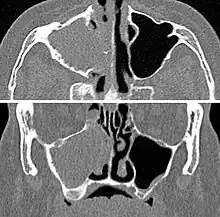

Chronic

For sinusitis lasting more than 12 weeks, a CT scan is recommended.[47] On a CT scan, acute sinus secretions have a radiodensity of 10 to 25 Hounsfield units (HU), but in a more chronic state they become more viscous, with a radiodensity of 30 to 60 HU.[49]